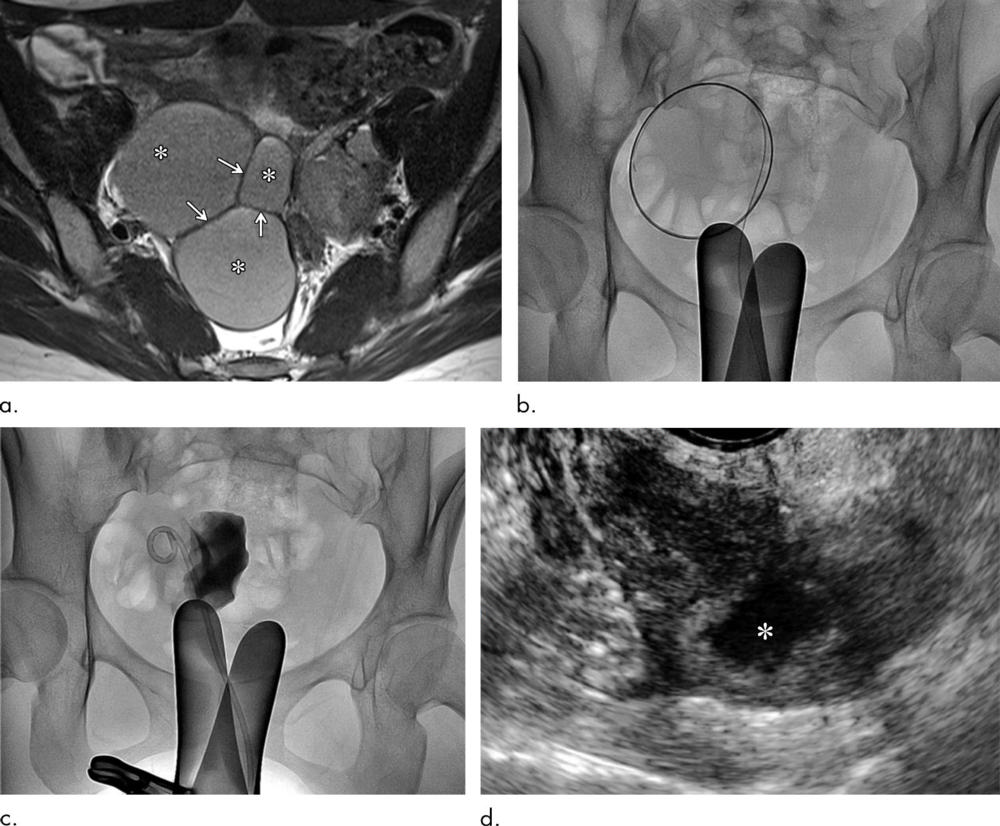

Figure 3. Clinical course of a 30-year-old woman with primary ovarian endometrioma presenting with lower abdominal pain. (a) Axial T2-weighted image shows a 7.1-cm, unilocular endometrioma (∗). (b) The endometrioma was punctured with transabdominal ultrasound (US) guidance. (c) A catheter was inserted and catheter-directed sclerotherapy (CDS) was performed. (d) Follow-up US 6 months after CDS reveals normal-looking ovary (O) without evidence of residual endometrioma.

High-res (TIF) version